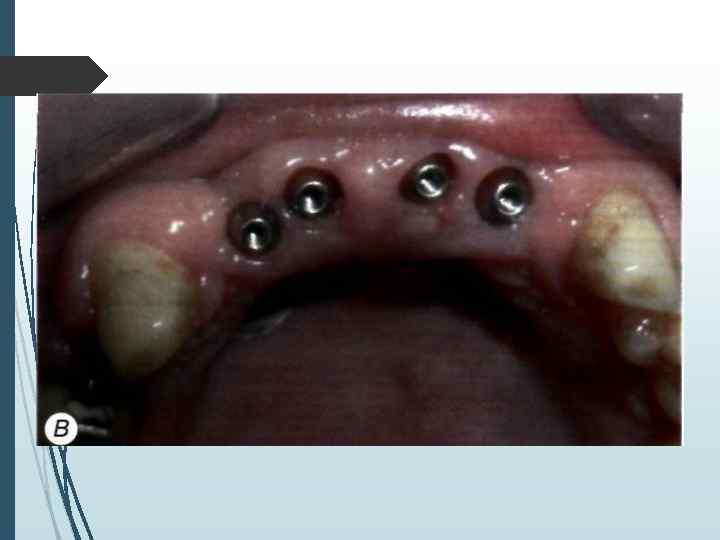

// этап Второй этап операции проводят через 2 3 мес. после установки внутрикостных элементов. Под местной инфи. тьтрапионной анестезией при помощи зонда определяют расположение внутрикостных элементов под слизистой оболочкой. Если из-за значительной ее толщины или нарастания костной ткани на внутрикост-ную часть и заглушку Определить расположение имплантата зондом невозможно, необходимо произвести разрез слизистой оболочки длиной до 10 мм в месте, где должен находиться внутрикостный элемент. Затем, отслаивая слизистую оболочку определяют расположение имплантата визуально. Иссечение слизистой оболочки над внутрикостным элементом производят перфоратором и удаляют иссеченный участок (рис. 11 -5). Выкручивают заглушку. Промывают внутренний резьбовой канал имплантата. Ввинчивают формирователь десневой манжетки, который на ортопедическом этапе. течения заменяют на опорную головку. Если производился разрез, рану зашивают узловыми швами.

А —- иссечение перфоратором слизистой оболочки и надкостницы над внутрикостным элементом; Б — выкручивание винта-заглушки: В — установка формирователя десневой манжетки